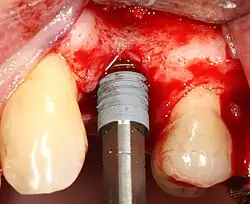

Most implant systems have five basic steps for placement of each implant:[28]: 214–221

- Soft tissue reflection: An incision is made over the crest of bone, splitting the thicker attached gingiva roughly in half so that the final implant will have a thick band of tissue around it. The edges of tissue, each referred to as a flap, are pushed back to expose the bone. Flapless surgery is an alternate technique, where a small punch of tissue (the diameter of the implant) is removed for implant placement rather than raising flaps.

- Drilling at high speed: After reflecting the soft tissue, and using a surgical guide or stent as necessary, pilot holes are placed with precision drills at highly regulated speed to prevent burning or pressure necrosis of the bone.

- Drilling at low speed: The pilot hole is expanded by using progressively wider drills (typically between three and seven successive drilling steps, depending on implant width and length). Care is taken not to damage the osteoblast or bone cells by overheating. A cooling saline or water spray keeps the temperature low.

- Placement of the implant: The implant screw is placed and can be self-tapping;[50]: 100–102 otherwise, the prepared site is tapped with an implant analog. It is then screwed into place with a torque controlled wrench[54] at a precise torque so as not to overload the surrounding bone (overloaded bone can die, a condition called osteonecrosis, which may lead to failure of the implant to fully integrate or bond with the jawbone).

- Tissue adaptation: The gingiva is adapted around the entire implant to provide a thick band of healthy tissue around the healing abutment. In contrast, an implant can be "buried", where the top of the implant is sealed with a cover screw and the tissue is closed to completely cover it. A second procedure would then be required to uncover the implant at a later date.